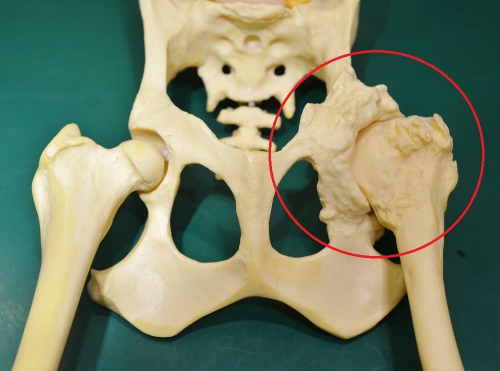

下の写真は股関節の重度の変形性関節症をしめす骨格モデルです。画面左の赤丸の中が重度に変形した関節構造をモデル化したものです。真ん中が正常な股関節で右がその部位の重度の変形関節症(拡大)です。

下は股関節の進行した変形性関節症のレントゲン写真です。赤丸の中が股関節ですが、大腿骨頭は変形して、関節内には骨棘の形成がみられます。同じ部位の正常写真が右です。

このワンちゃんは日常的に下肢の痛みを訴えており、運動状態によって、また寒い時期に悪化がみられます。後ろ足には常に痛みがあり、充分に動かすことができません。